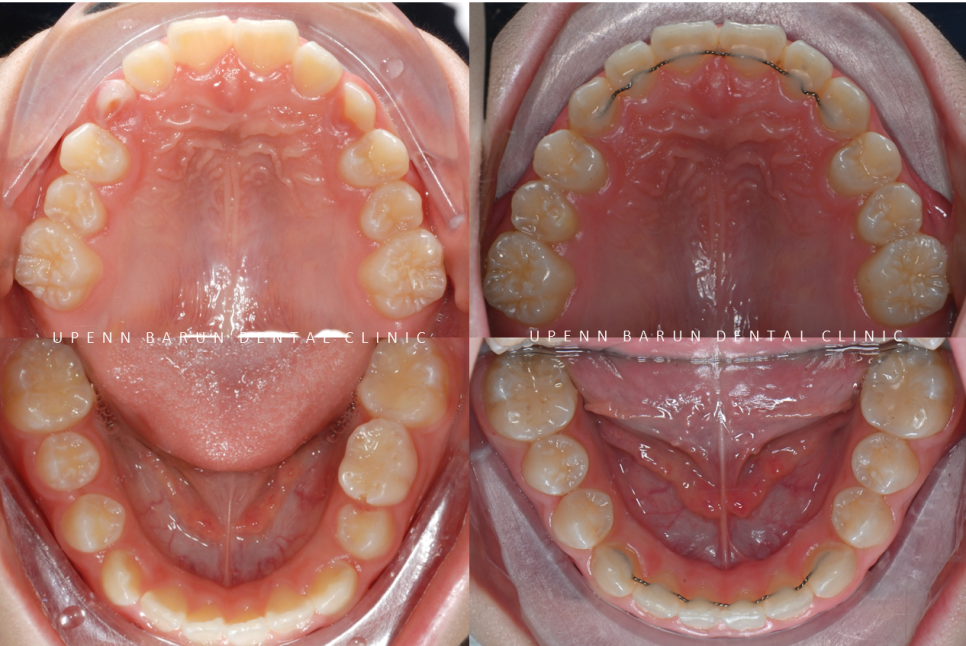

교정기간 23/8~24/10

마지막 클린체크를 통해

교정이 마무리된 사진입니다 :)

영구치 교환시기에 시작한 인비절라인은

어린이 환자들에게 맞춤형 기능을 제공하고

악궁확장과 함께 맹출중인 영구치의 공간확보에 유리합니다.

또한

악궁형태 발달, 맹출중인 치열공간 유지 등 광범위한 부정교합에 대한 치료를 제공합니다.